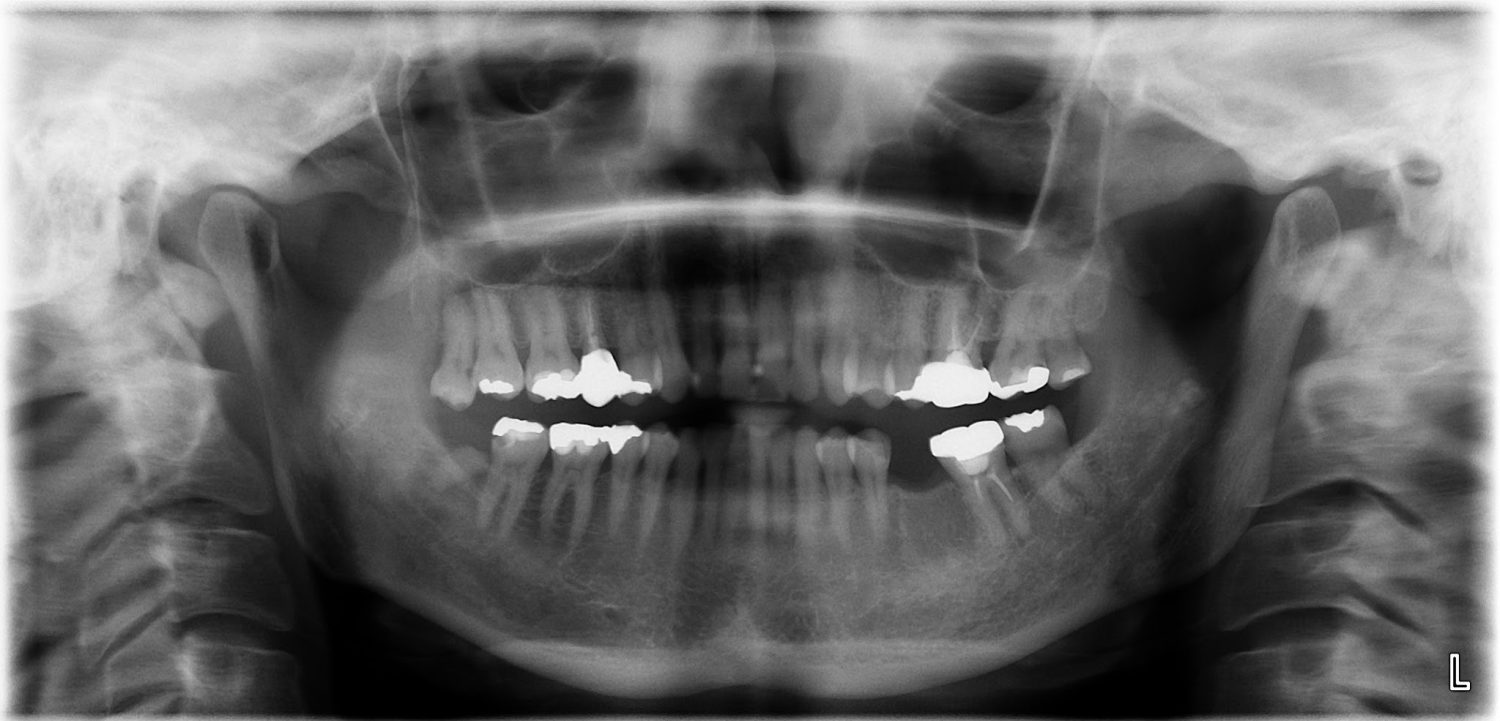

インプラント治療の症例紹介④

Before

After

主訴

義歯による疼痛

治療内容

下顎舌側に骨隆起があり義歯困難な状態。保存不可能な歯の抜歯を行い、インプラントを埋入し咬合再構成を行った。

治療費

2,851,200円(税込)

治療期間

29ヶ月

通院回数

26回

想定されたリスク

※咬合力の強い方なので、予防的にマウスピースの装着が必要。インプラント周囲炎の恐れがありました。

濱 仁隆先生

浜歯科

歯の欠損の対合歯の挺出等を修正し咬合平面を揃え咬合再構成を行った症例。